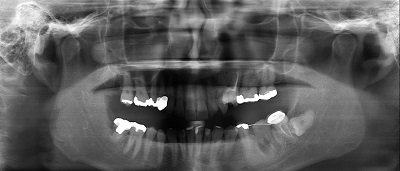

レントゲン撮影・CT撮影・口腔内Scan ・シュミレーションソフトによるプランニング

インプラント予定部位の骨の状態、周囲組織の状態を診査します。CTを用いることで多角的に診断することができます。当院では最新の歯科用コーンビームCTを設置し、低被爆を実現しています。

全身状態の把握をするため、問診、血液検査、生体モニターによるバイタルのチェック等、またインプラントを埋入する骨の状態、その後のかみ合わせを考慮した方向性や周辺組織の状態を確認するため、レントゲン撮影及びCT撮影を行いシュミレーションソフトを使用使用し、総合的に治療計画を立案していきます。また、必要に応じて近隣医療機関との連携を行います。

当院では最新のドイツKavo 社製のCTを設置しています。

低被爆で細かな診断と埋入シュミレーションを行い診断をしております。